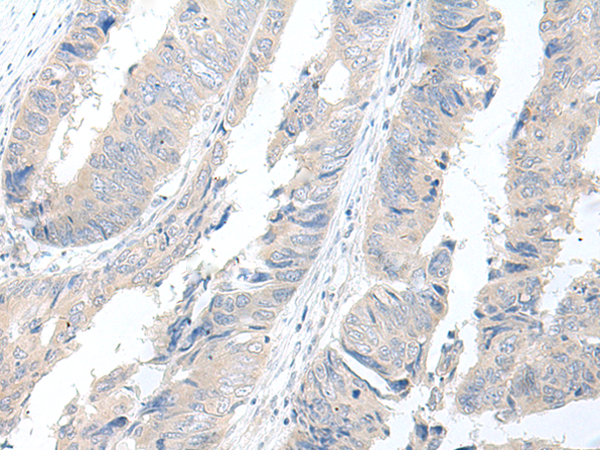

IHC positive control: |

Human colorectal cancer |

IHC Recommend dilution: |

50-300 |